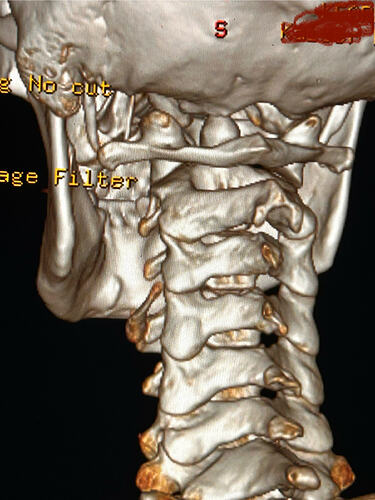

Here are some images of my 3-d ct, thanks for taking an interest it means a lot!

Oh and I almost forgot these were taken before I had my right styloidectomy

Things of note that I can see in your imaging - You’ve completely lost the natural lordotic curve in your cervical spine. That alone can bring the styloids & hyoid bone into closer proximity to nerves & vascular tissues in the neck though it has been speculated that the neck curve is lost when there’s IJV compression due to ES as the body’s way of trying to create more space for the IJV so it can drain the deoxygenated blood from the brain more efficiently. The lordotic curve can be restored w/ gentle exercises but it takes patience & is a slow process. The following link has helpful information about cervical curve restoration.

In this image of your left styloid, it appears from the angle of the picture that your left styloid is extremely close to the left transverse process of C1 (green circled area). If that’s truly the case, your left IJV is likely being squashed between the two & that means your vagus nerve is most likely being squashed at that point, too. Some of your symptoms could be vagal related. Also due to the angle of the image, it appears the greater horn of your hyoid could be very close to your spine which can cause internal/external carotid artery compression but can also cause symptoms that point to hyoid bone syndrome as you’ve suggested. Unfortunately, it doesn’t appear the CT scan was done w/ contrast as none of your veins or arteries appear in the images you posted & contrast is necessary to see those.

I’ll just add in as well that in your first image, the hyoid bone processes look pretty thick, more than you’d expect, so could well be part of your issues, but I do agree with @Isaiah_40_31 that your left styloid is very close to the C1 process, the right side looks a little longer than average… Also looking at the 1st & last images (I’m sorry, | can’t label them for you), there’s calcification below your hyoid which I’m presuming is the thyroid cartilage, it lookd pretty chunky compared to most people’s, so this could possibly be causing some issues too?

I totally missed that I could see your whole hyoid bone from the front in this image. Jules is right, your greater horns are very thick from top to bottom. You can also see that your left greater horn is pretty straight, but the right one has an upward curve to it. I’m not sure what the calcification is below your hyoid but it’s most likely thyroid since the thyroid sits just below the hyoid in the neck.

In this image, you can see the differences in the shapes of your hyoid’s greater horns. The right one is more curved but the left one is thicker in width medial to lateral. In this image from the front it looks like both greater horns may be contacting your cervical spine in certain head positions, but again, that may an illusion created by the angle of the image.